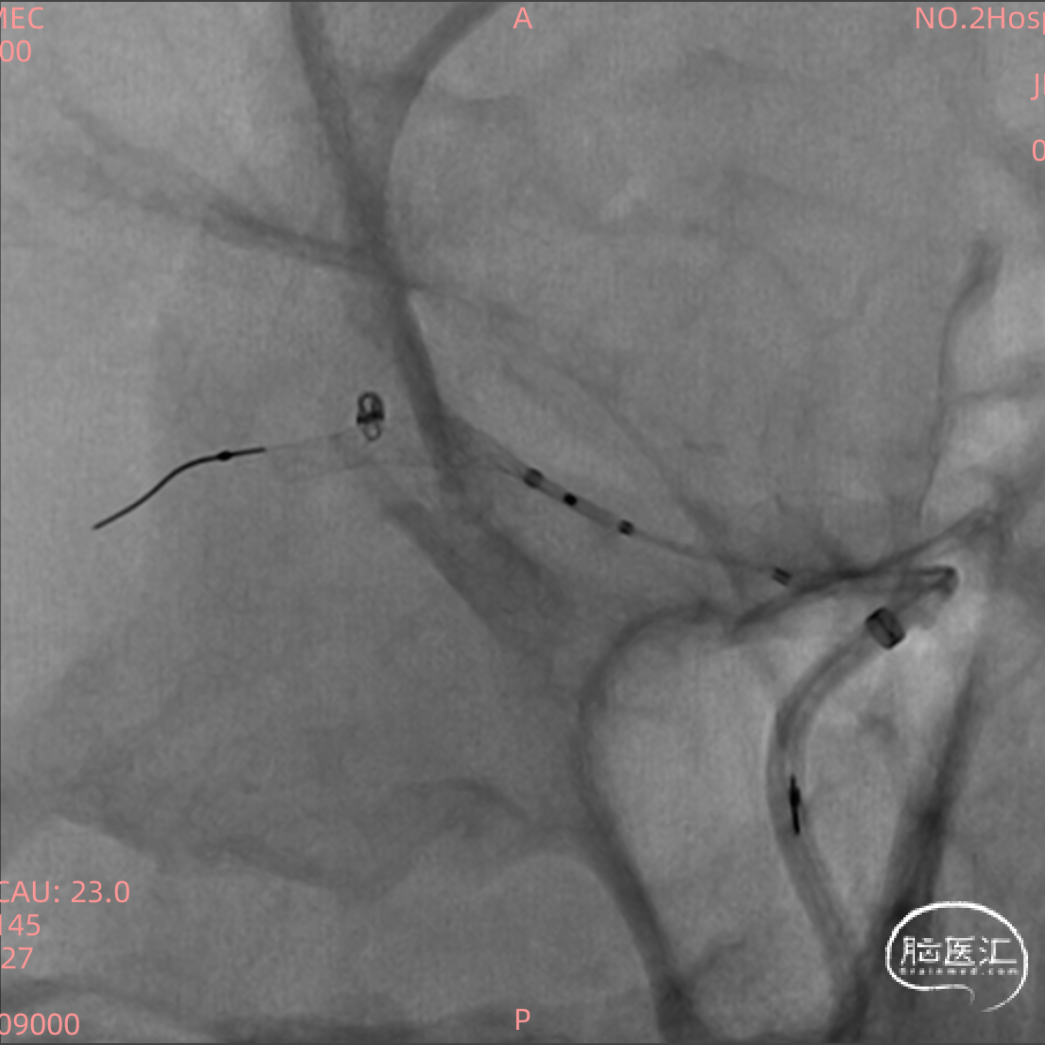

根据造影结合患者头部CT出血分布考虑朝上方的较大动脉瘤(1.3mm*1.2mm)为破裂出血的责任动脉瘤,但是其瘤体小难以致密填塞,并且朝下的微小动脉瘤约0.8mm,难以进行弹簧圈填塞,故考虑破裂动脉瘤予以1枚弹簧圈疏松填塞加快瘤内血栓形成后置入密网支架覆盖上下两枚动脉瘤进行血管壁修复。

测量血管远端1.5mm,近端2.5mm,支架直径选择3.25mm,因为该部位有豆纹动脉发出,故考虑选择一枚短支架(15mm),尾端置于大脑中动脉M1段远端1/3。

密网支架:FD Surpass Evolve 3.25mm*15mm

Synchro2+XT-27通过中间导管超选至动脉瘤远端,撤出导丝。

直接将导丝放入微小破裂动脉瘤内超选微导管风险极高,故将SL-10导管头端进行“S”塑形后,将SL-10导管先置于动脉瘤远端血管后再回拉弹入动脉瘤内填塞1mm*2mm(Target)弹簧圈。

远端释放技术:

系统在M2段退管,支架打开约5mm后回拖,通过轻推回拉使支架缓慢释放,非常顺畅。

中段释放技术:

远端释放支架后,保持XT-27位于血管中间位置,为更好贴壁,轻推系统,中段缓慢释放。

近端释放技术:

轻推后卸张力,保持微导管居中,撤微导管,支架完全打开,XT-27跟进。

大脑中动脉多发微小动脉瘤,并且微小动脉瘤破裂相对少见,Surpass Evolve支架的释放及贴壁非常丝滑,操作简单,此病例难度在于微小破裂动脉瘤的弹簧圈填塞,并且支架释放过程中对微导管的影响较小。